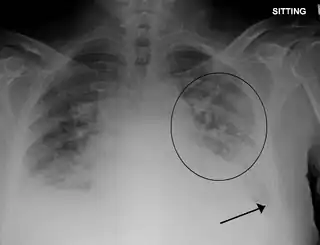

![]() Radiografía de tórax con edema pulmonar y pequeños derrames pleurales bilaterales | ||

- Una radiografía de tórax que puede revelar líquido en o alrededor del espacio pulmonar o un agrandamiento del corazón.